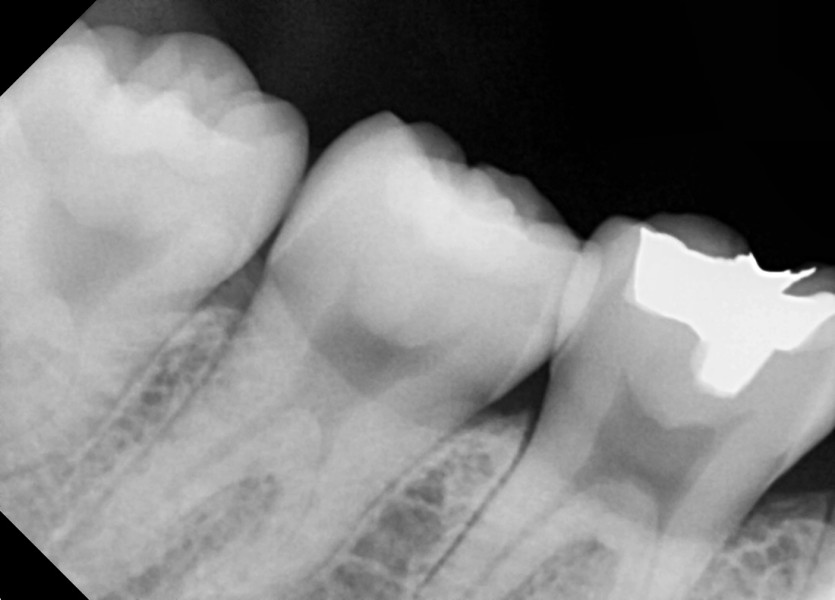

#38,48 사랑니 발치

구강 외과 전문의가 당일 발치했습니다.